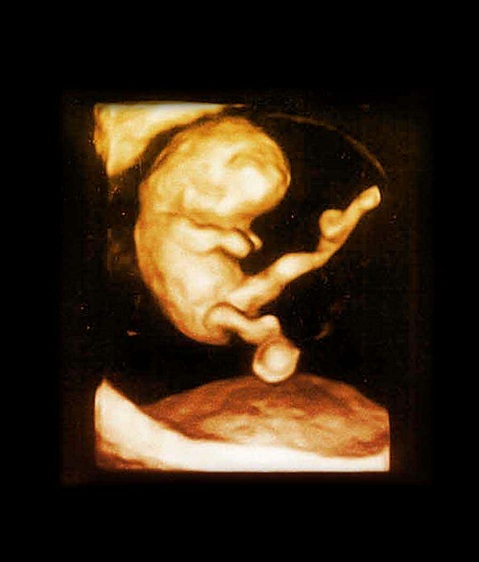

胎儿图

三维图

8周过去了,你的胚胎从现在开始可以称为“胎儿”了,也可以称之为“小宝宝”。为了接纳新居民,你的子宫膨胀得非常大,现在胎儿的尺寸大约有25毫米,而且胎儿许多位置都有所改变,如胚胎期的小尾巴不见了等。现在所有的器官、肌肉、神经开始工作。手部从手腕开始变得稍微有些弯曲,双脚开始摆脱蹼状的外表,眼帘开始覆盖住眼睛。